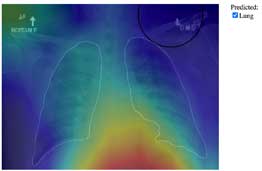

Pneumonia in Chest

(X-ray image)

- Automatic lung detection

- Highlight pneumonia location

- Classification with percentage